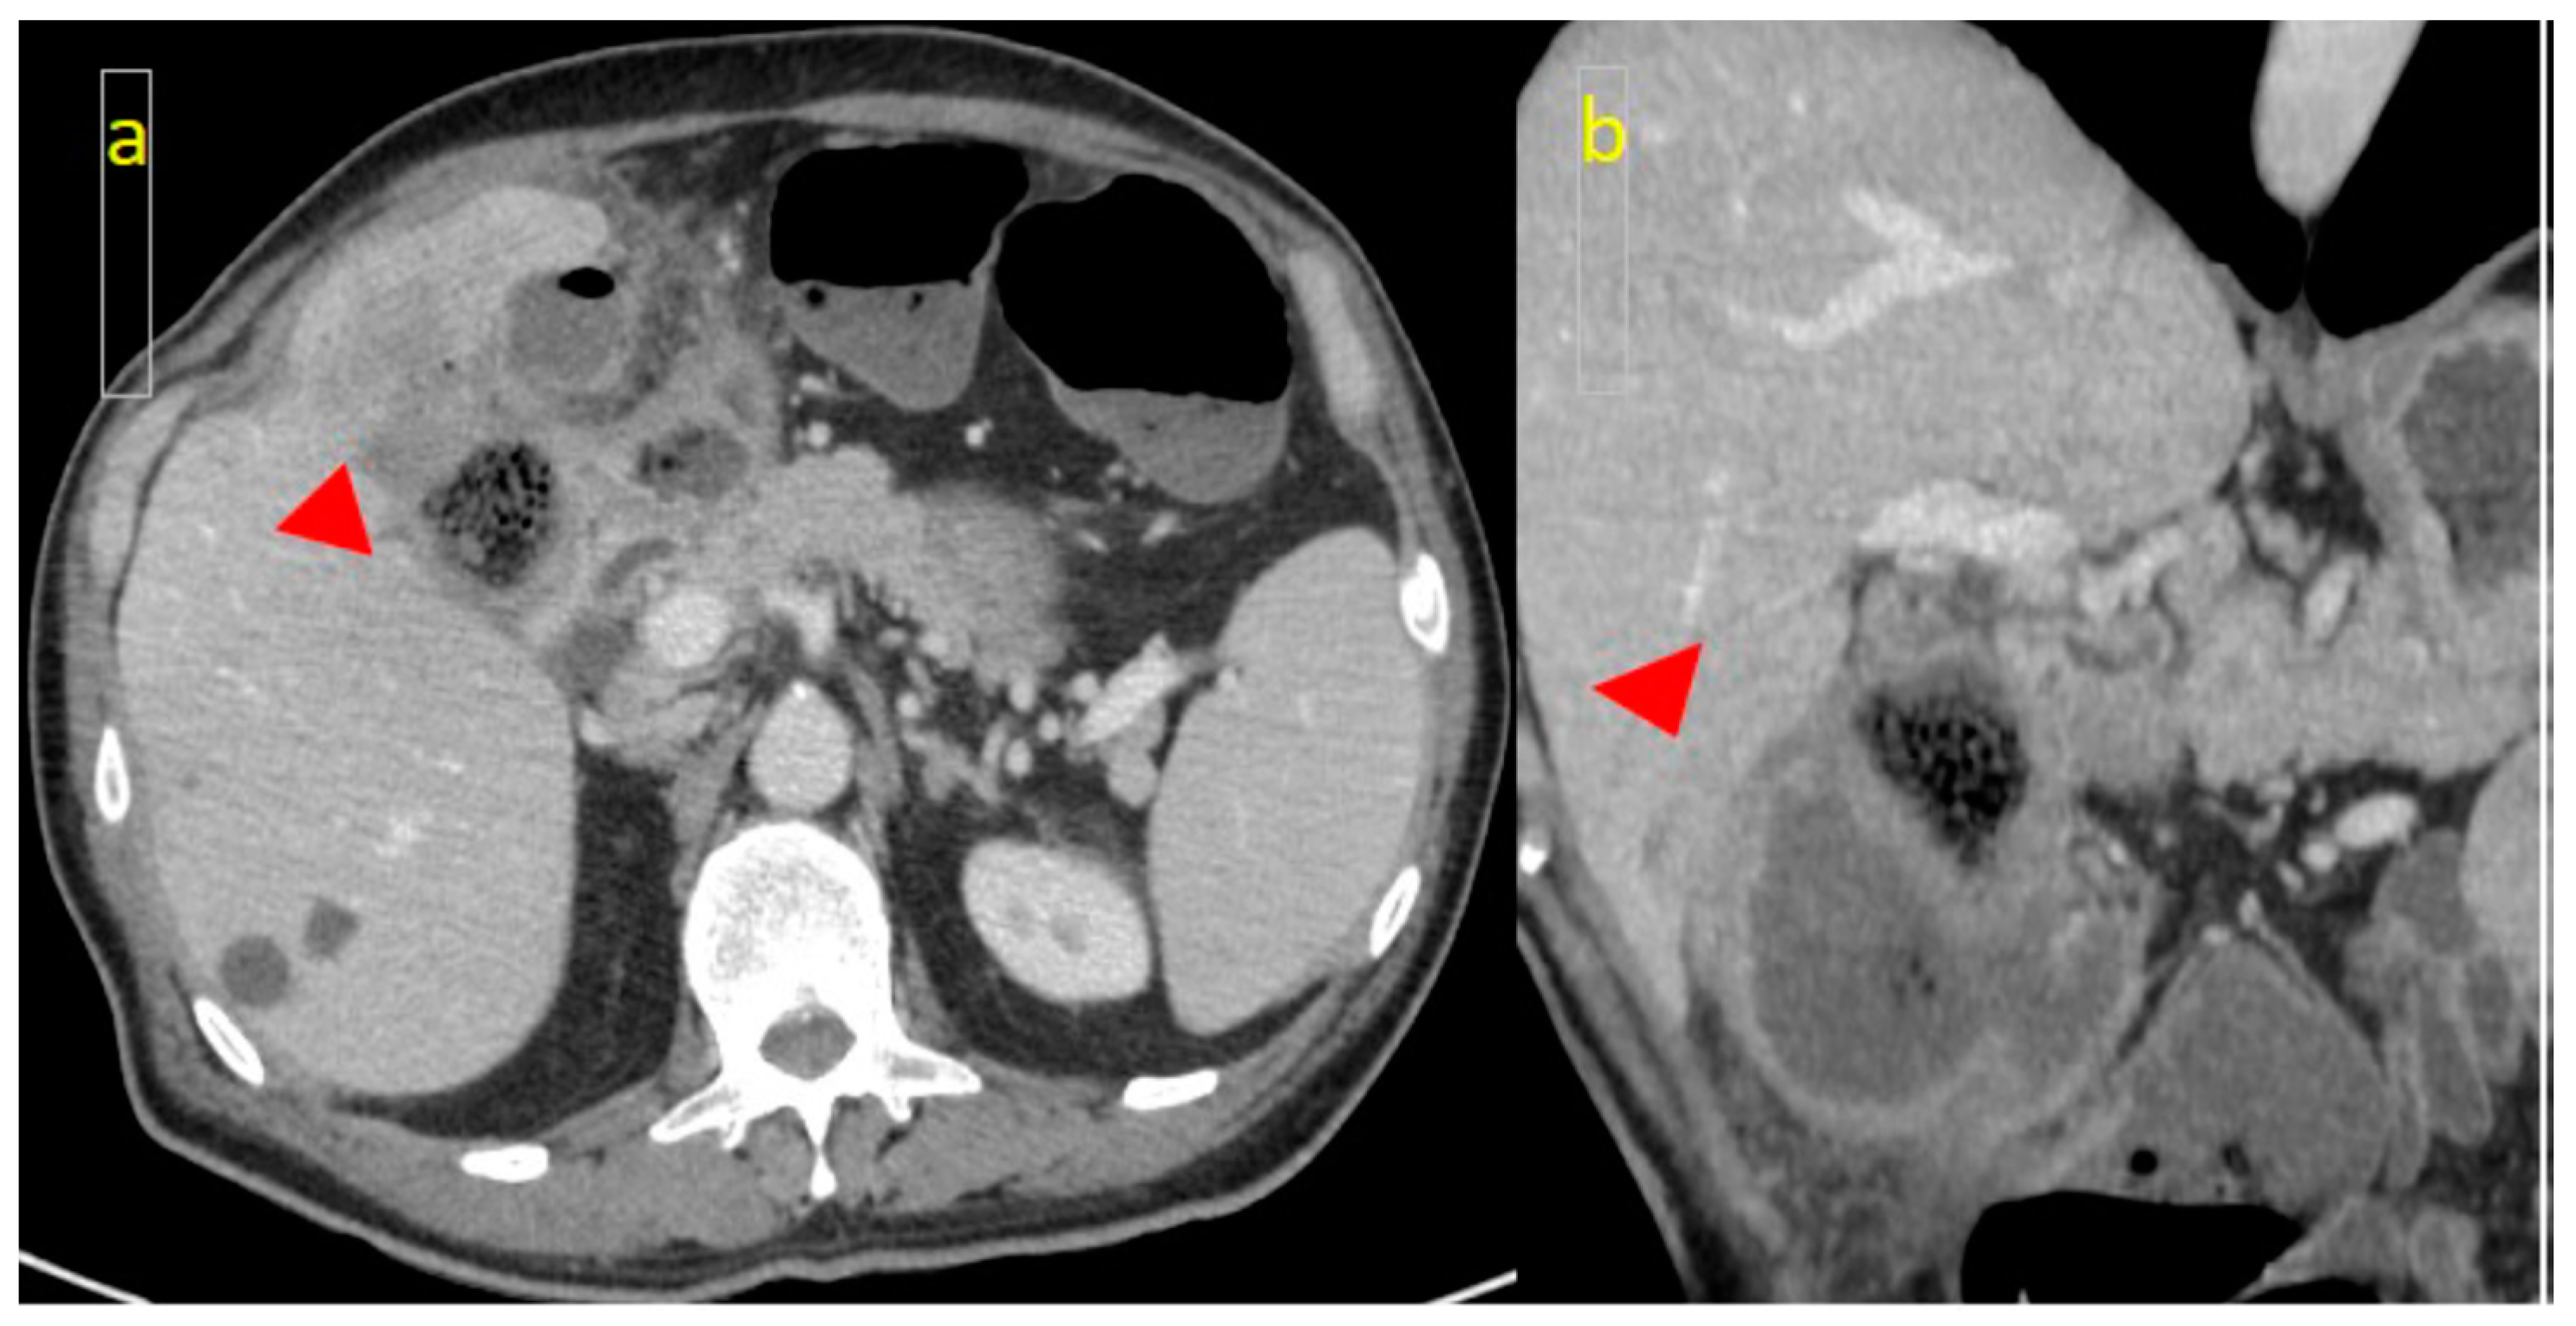

2. Case Report